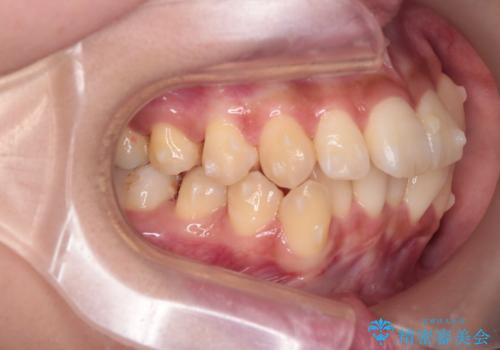

反対咬合を治したい。インビザライン

- 前歯の反対咬合を治したいことを主訴に来院されました。

インビザラインにて臼歯の遠心移動を行いながら、スペースを作り反対咬合を改善することができました。